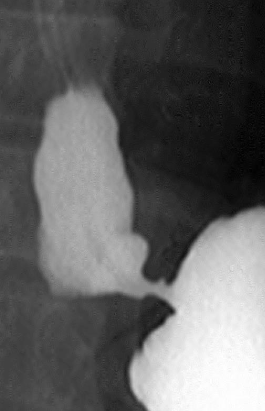

Pneumoperitoneu